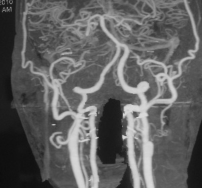

Hình 3.2b. Minh họa tắc động mạch cảnh trong hai bên - hai ca còn lại: TVG 74 tuổi (trái) và VHK 48 tuổi (giữa và phải), có tổn thương nhỏ vùng ranh giới, tắc động mạch cảnh trong hai bên với bàng hệ Willis từ hệ đốt sống thân nền qua động mạch thông sau.

Có 3 bệnh nhân (2,5%) tắc hoàn toàn động mạch cảnh trong đối bên, nghĩa là tắc động mạch cảnh trong cả hai bên (Hình 3.2 a,b). Ba mươi bệnh nhân (24,8%) có động mạch cảnh trong đối bên hoàn toàn bình thường. Còn lại đại đa số bệnh nhân có xơ vữa hẹp một phần động mạch cảnh trong đối bên (n=88; 72,7%, trong đó 7,4% hẹp nặng, 65,3% hẹp nhẹ).